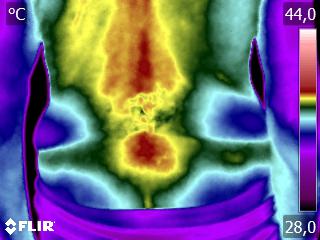

Caros colegas fisioterapeutas e terapeutas ocupacionais, vocês sabiam que, por meio do estudo da Termofuncional, é possível identificar alterações térmicas […]

Caros colegas fisioterapeutas e terapeutas ocupacionais, vocês sabiam que, com o estudo da técnica Termofuncional, é possível identificar alterações térmicas […]